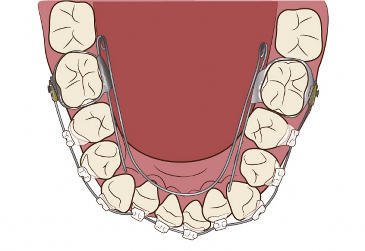

取り組み3:歯並びの改善

現代の子供たちは顎の成長が十分でなく、歯並びが悪くなることが多いです。当院では、「プレオルソ」というマウスピース型の装置を使った矯正治療を行っています。この装置は日中1時間と就寝時のみの装着で、口周りの筋肉を整え、歯並びを改善します。

小児矯正治療

小児矯正治療について詳しく知りたい方は、「子どもの歯並び改善」をご参照ください。当院では小児歯科専門医と矯正歯科認定医が担当し、お子様の歯並びを改善します。